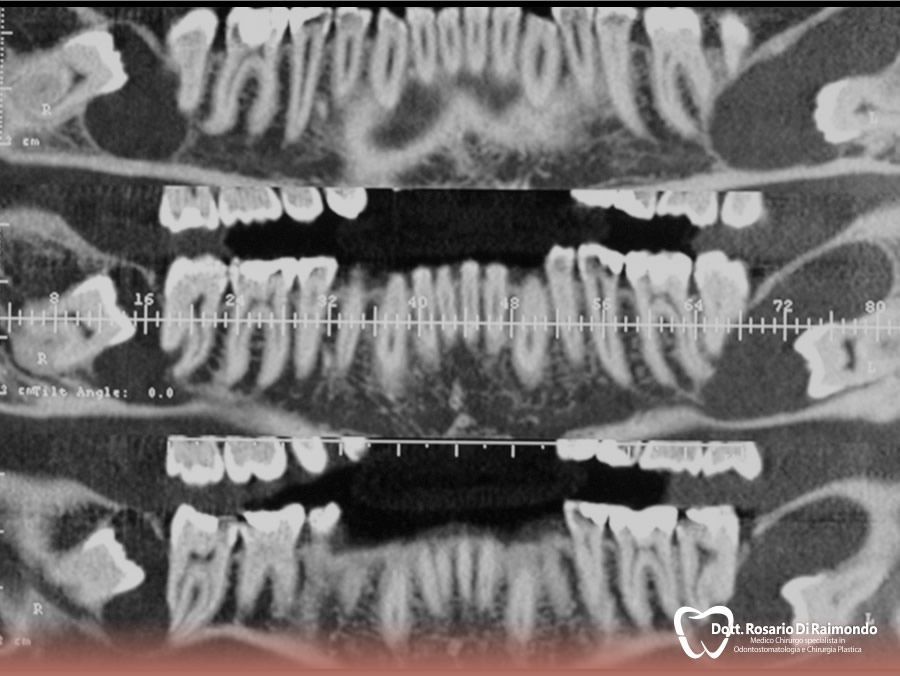

Casi Trattati

Di seguito riportiamo alcune fotografie di casi esplicativi di Chirurgia Orale.